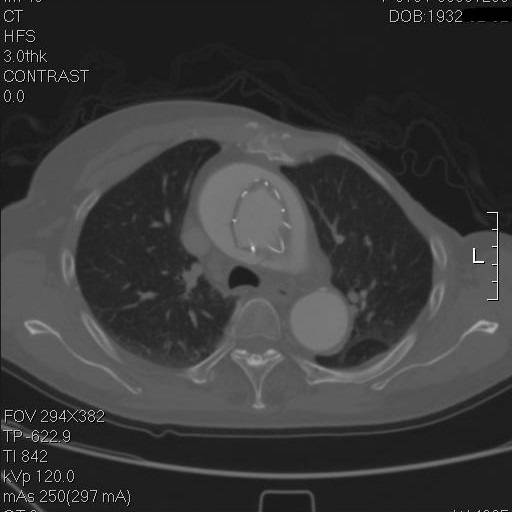

再往上,这个支架竟然是骑跨在真假腔之间的!

这个层面,支架终于完全在真腔内了,但假腔基本没有闭合。

到弓部可以看到,支架远端贴得倒还可以